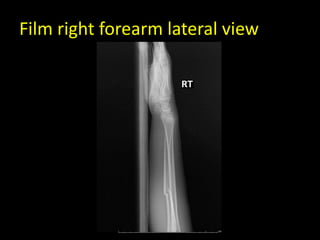

Film right forearm lateral view

• Film : minimally displaced fracture midshaft

both bone of right forearm

• Diagnosis : Close fracture both bone right

forearm

Film right forearmlateral view

• Film :minimally displaced fracture midshaft both bone of right forearm • Diagnosis : Close fracture both bone right forearm